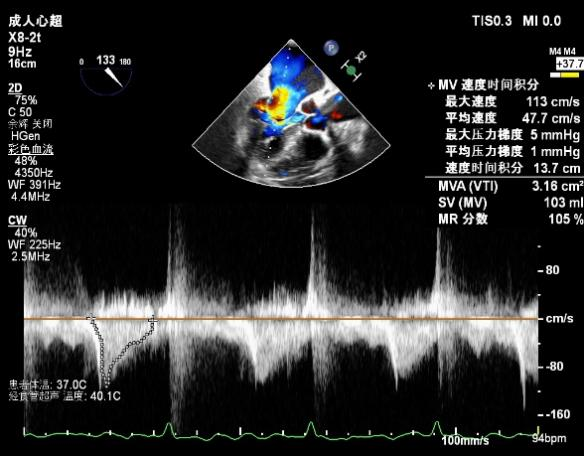

肺静脉血流频谱逐渐恢复正向,后测量平均跨瓣压差:2mmHg

肺静脉血流频谱恢复正向

二尖瓣瓣口平均跨瓣压差:3mmHg